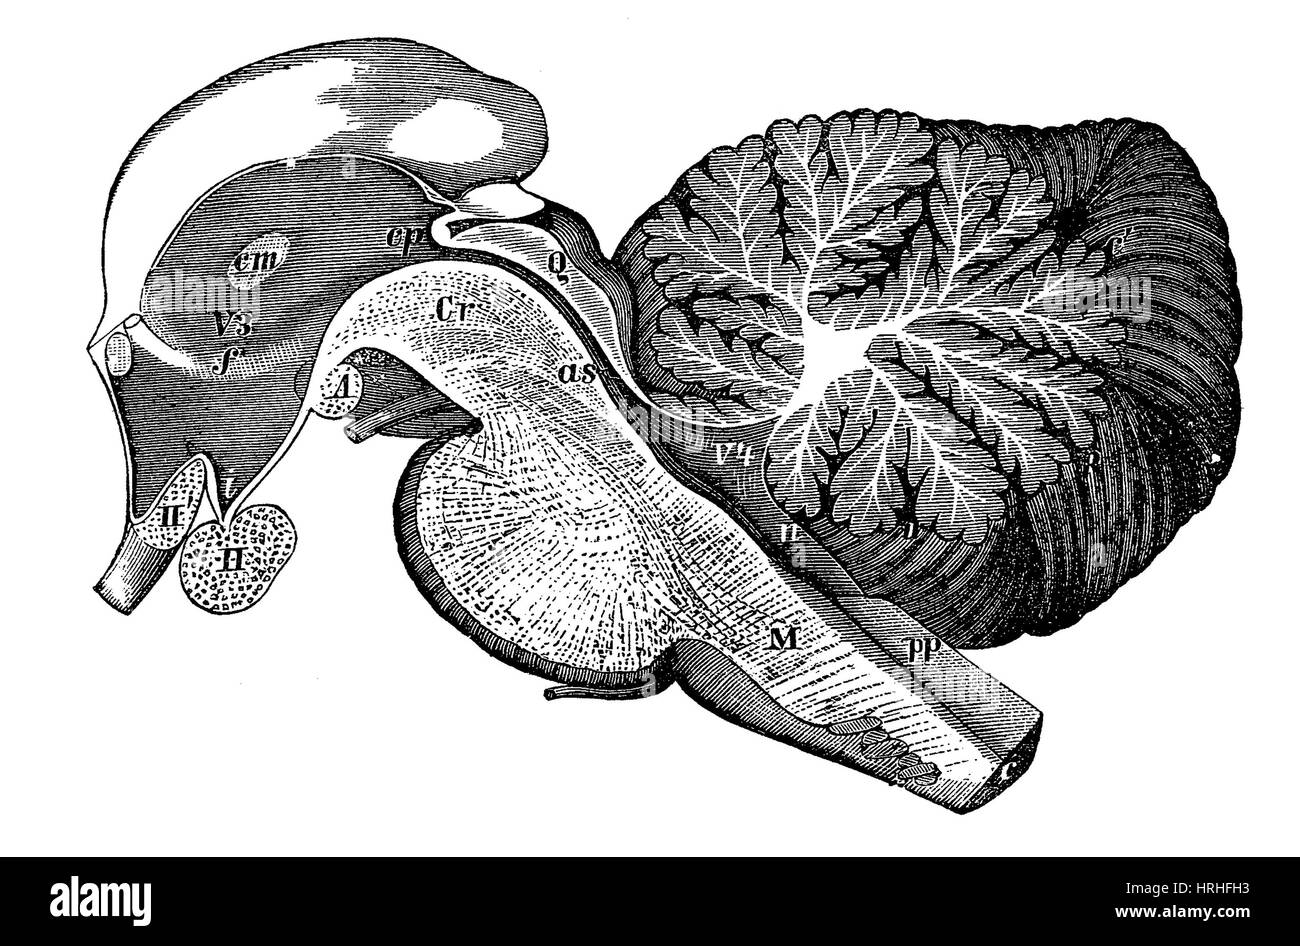

RM2ANEPH2–Die encyclopdia Britannica; ein Wörterbuch der Künste, Wissenschaften, Literatur und allgemeinen Informationen. Trakt. Der dritten Ventrikel (siehe Abb. 6) isa Hohlraum im mesialplane zwischen den beiden Optic thalami gelegen. Sein Dach ist durch die veluminterpositum und Körper der fornix gebildet; der Fußboden durch die posteriorperforated Raum, Korpora ajbicantia, Tuber cinereum, infundibulum und Optic commissure; seine vordere Begrenzung durch die anteriorpillars Der fornix, anterior Commissure und lamina cinerea; itsposterior Begrenzung durch den Corpora quadrigemina und posteriorcommissure. Den Hohlraum der Ventrikel ist o

RM2CDFE0C–. Elemente der physiologischen Psychologie; eine Abhandlung über die Aktivitäten und die Natur des Geistes, aus der physischen und experimentellen Gesichtspunkten. ide,die corpora quadrigemina. Die Kavität des Neuralrohres bleibt hier klein und bildet das Aquädukt, das den Viertmit dem dritten Ventrikel verbindet. Im Zwischenhirn dehnt sich das Aquädukt in den dritten Ventrikel aus; und hier wird wieder die dorsale Wand des Tubus zu einer breiten, dünnen Membran, die in den Ventrikel gefaltet und Blutgefäße mit sich trägt. Während die zerebralen Hemisphären ihr enormes Wachstum durchlaufen, dehnt sich die Kavität mit ihnen aus, andrema

RMG155NT–Illustration einer sagittalen Abschnitt der dritten und vierten Ventrikel des Gehirns. Die Ventrikel enthalten Liquor cerebrospinalis, die das Gehirn dämpft. Dies ist eine historische Darstellung aus den 1890er Jahren.